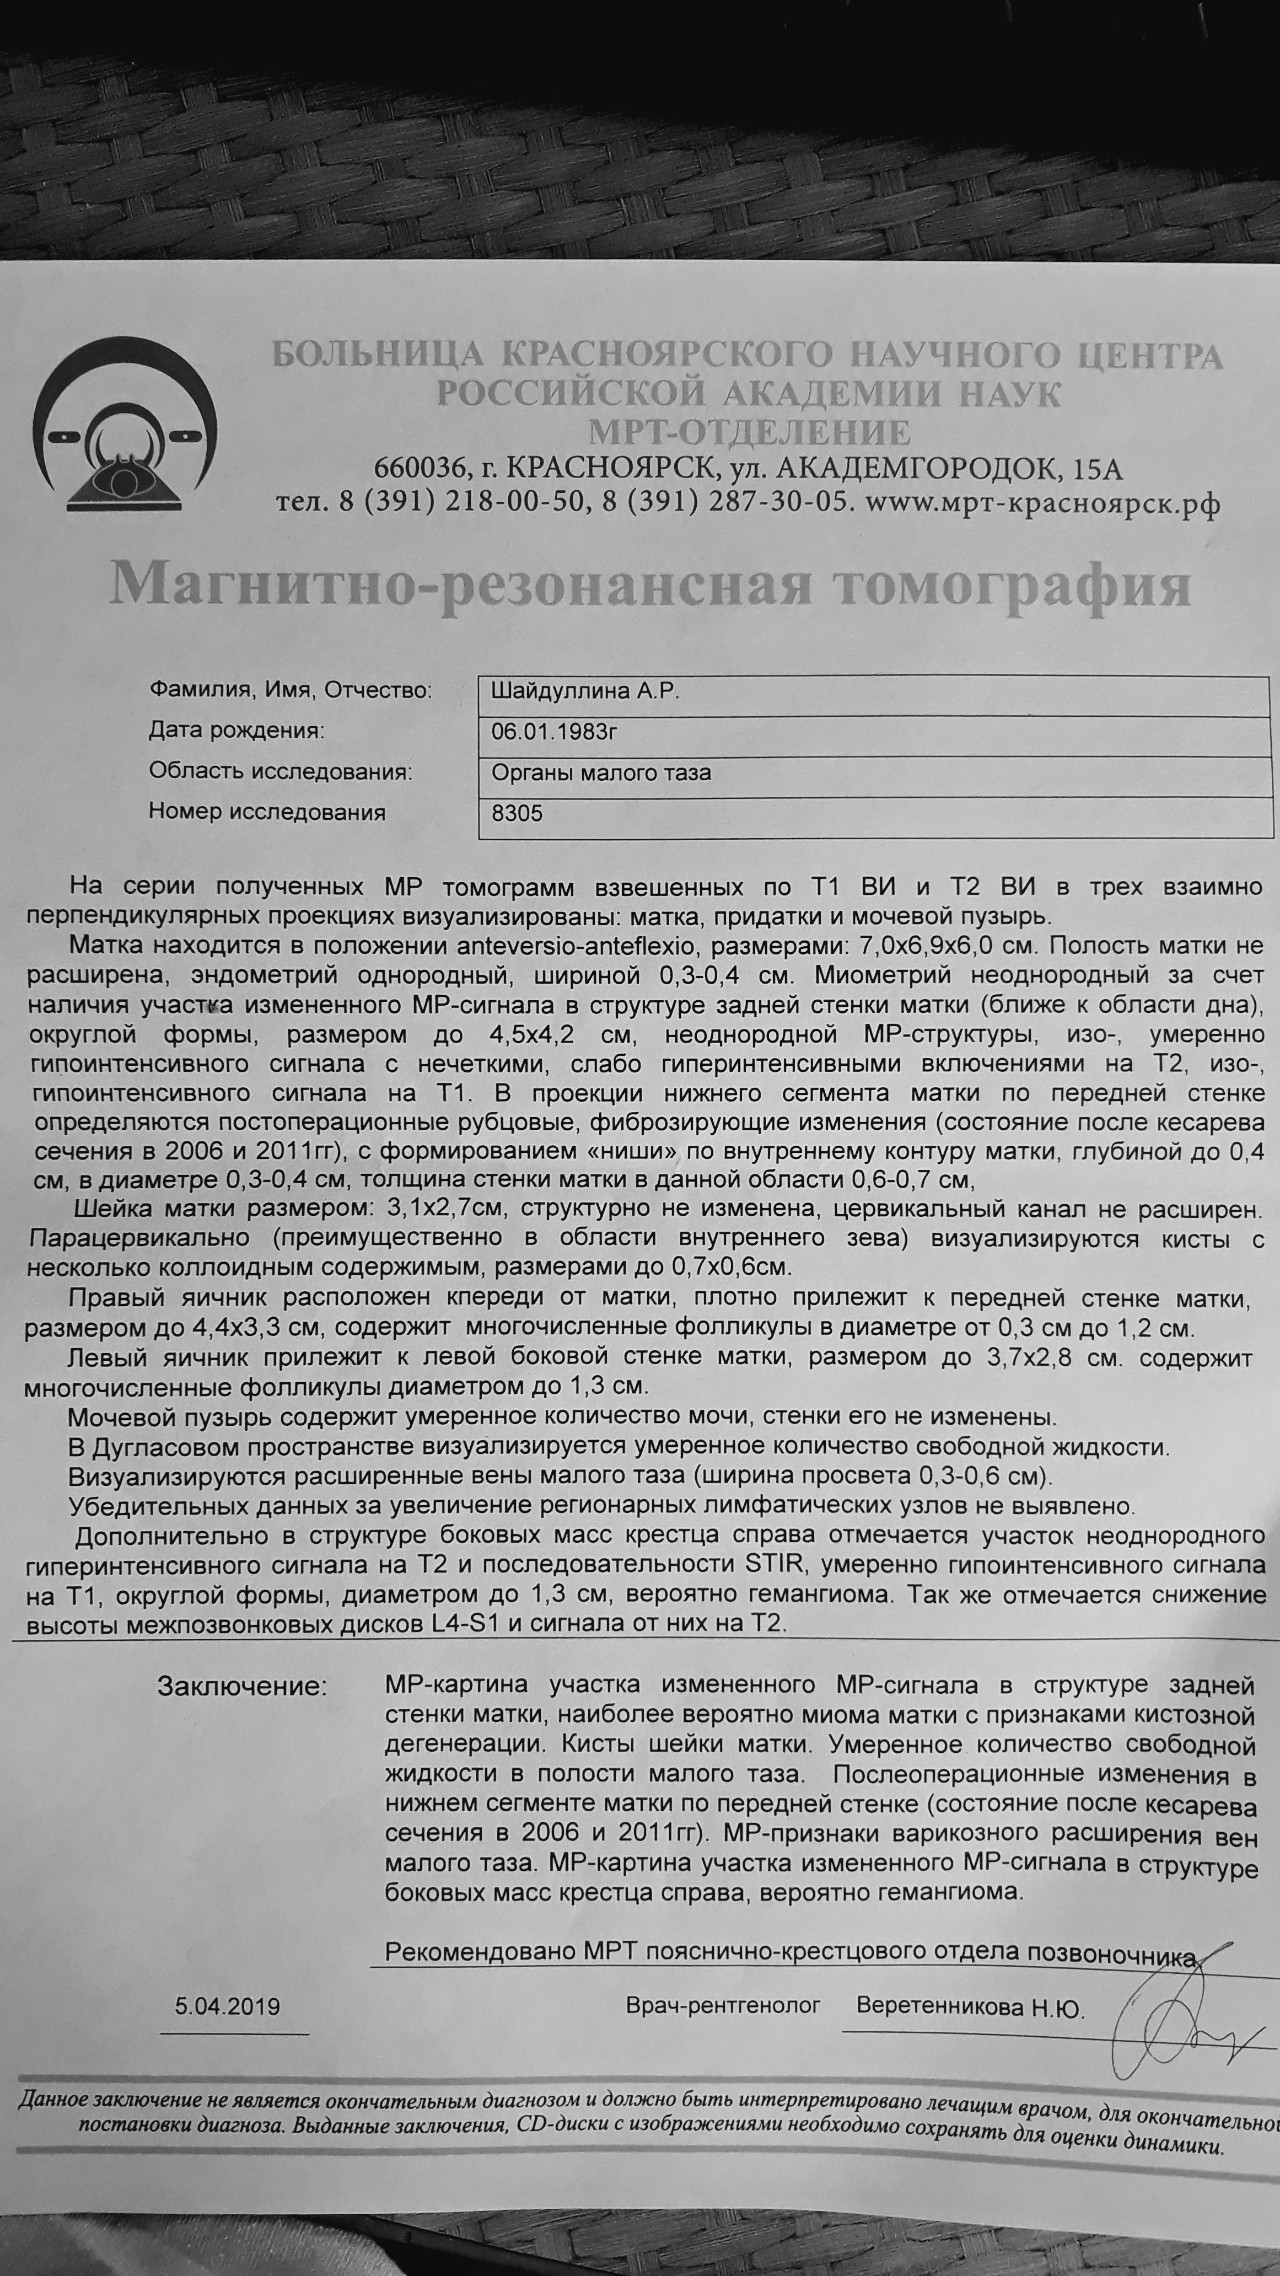

Магнитно-резонансная томография (МРТ) малого таза у женщин является важным методом диагностики различных заболеваний. На фотографиях МРТ можно увидеть органы малого таза, такие как матка, яичники, мочевой пузырь, прямая кишка и другие структуры.

Примеры фото МРТ малого таза у женщин

Ниже представлены примеры фотографий МРТ малого таза у женщин, позволяющие увидеть, как выглядят снимки и какие изменения могут быть обнаружены специалистами.